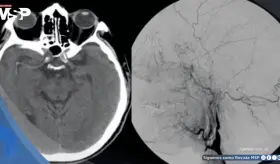

Este caso destaca la importancia de considerar etiologías supratentori...

La paciente presentaba múltiples factores de riesgo incluyendo uso de ...